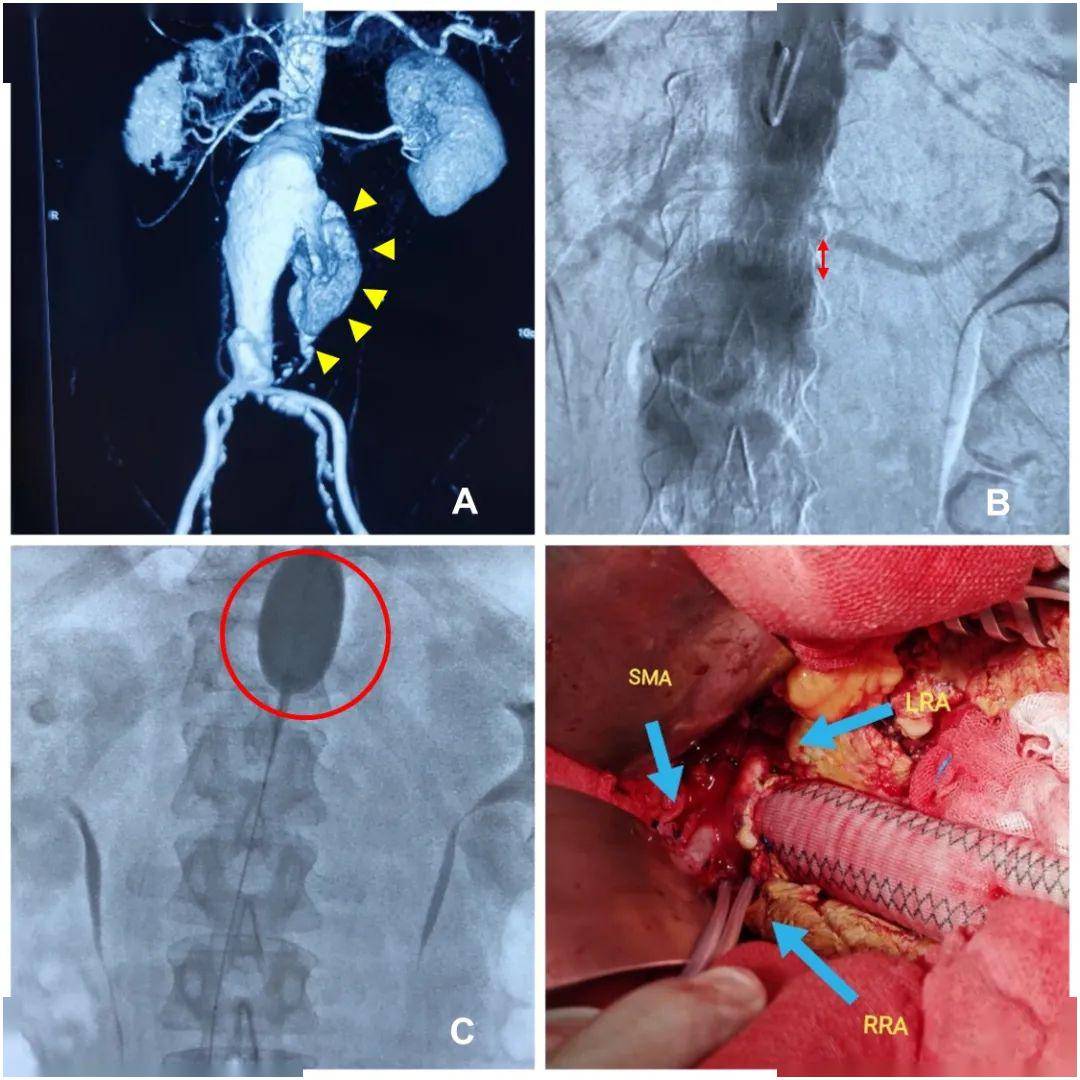

感染性破裂腹主动脉瘤手术治疗

图片尺寸3456x4608